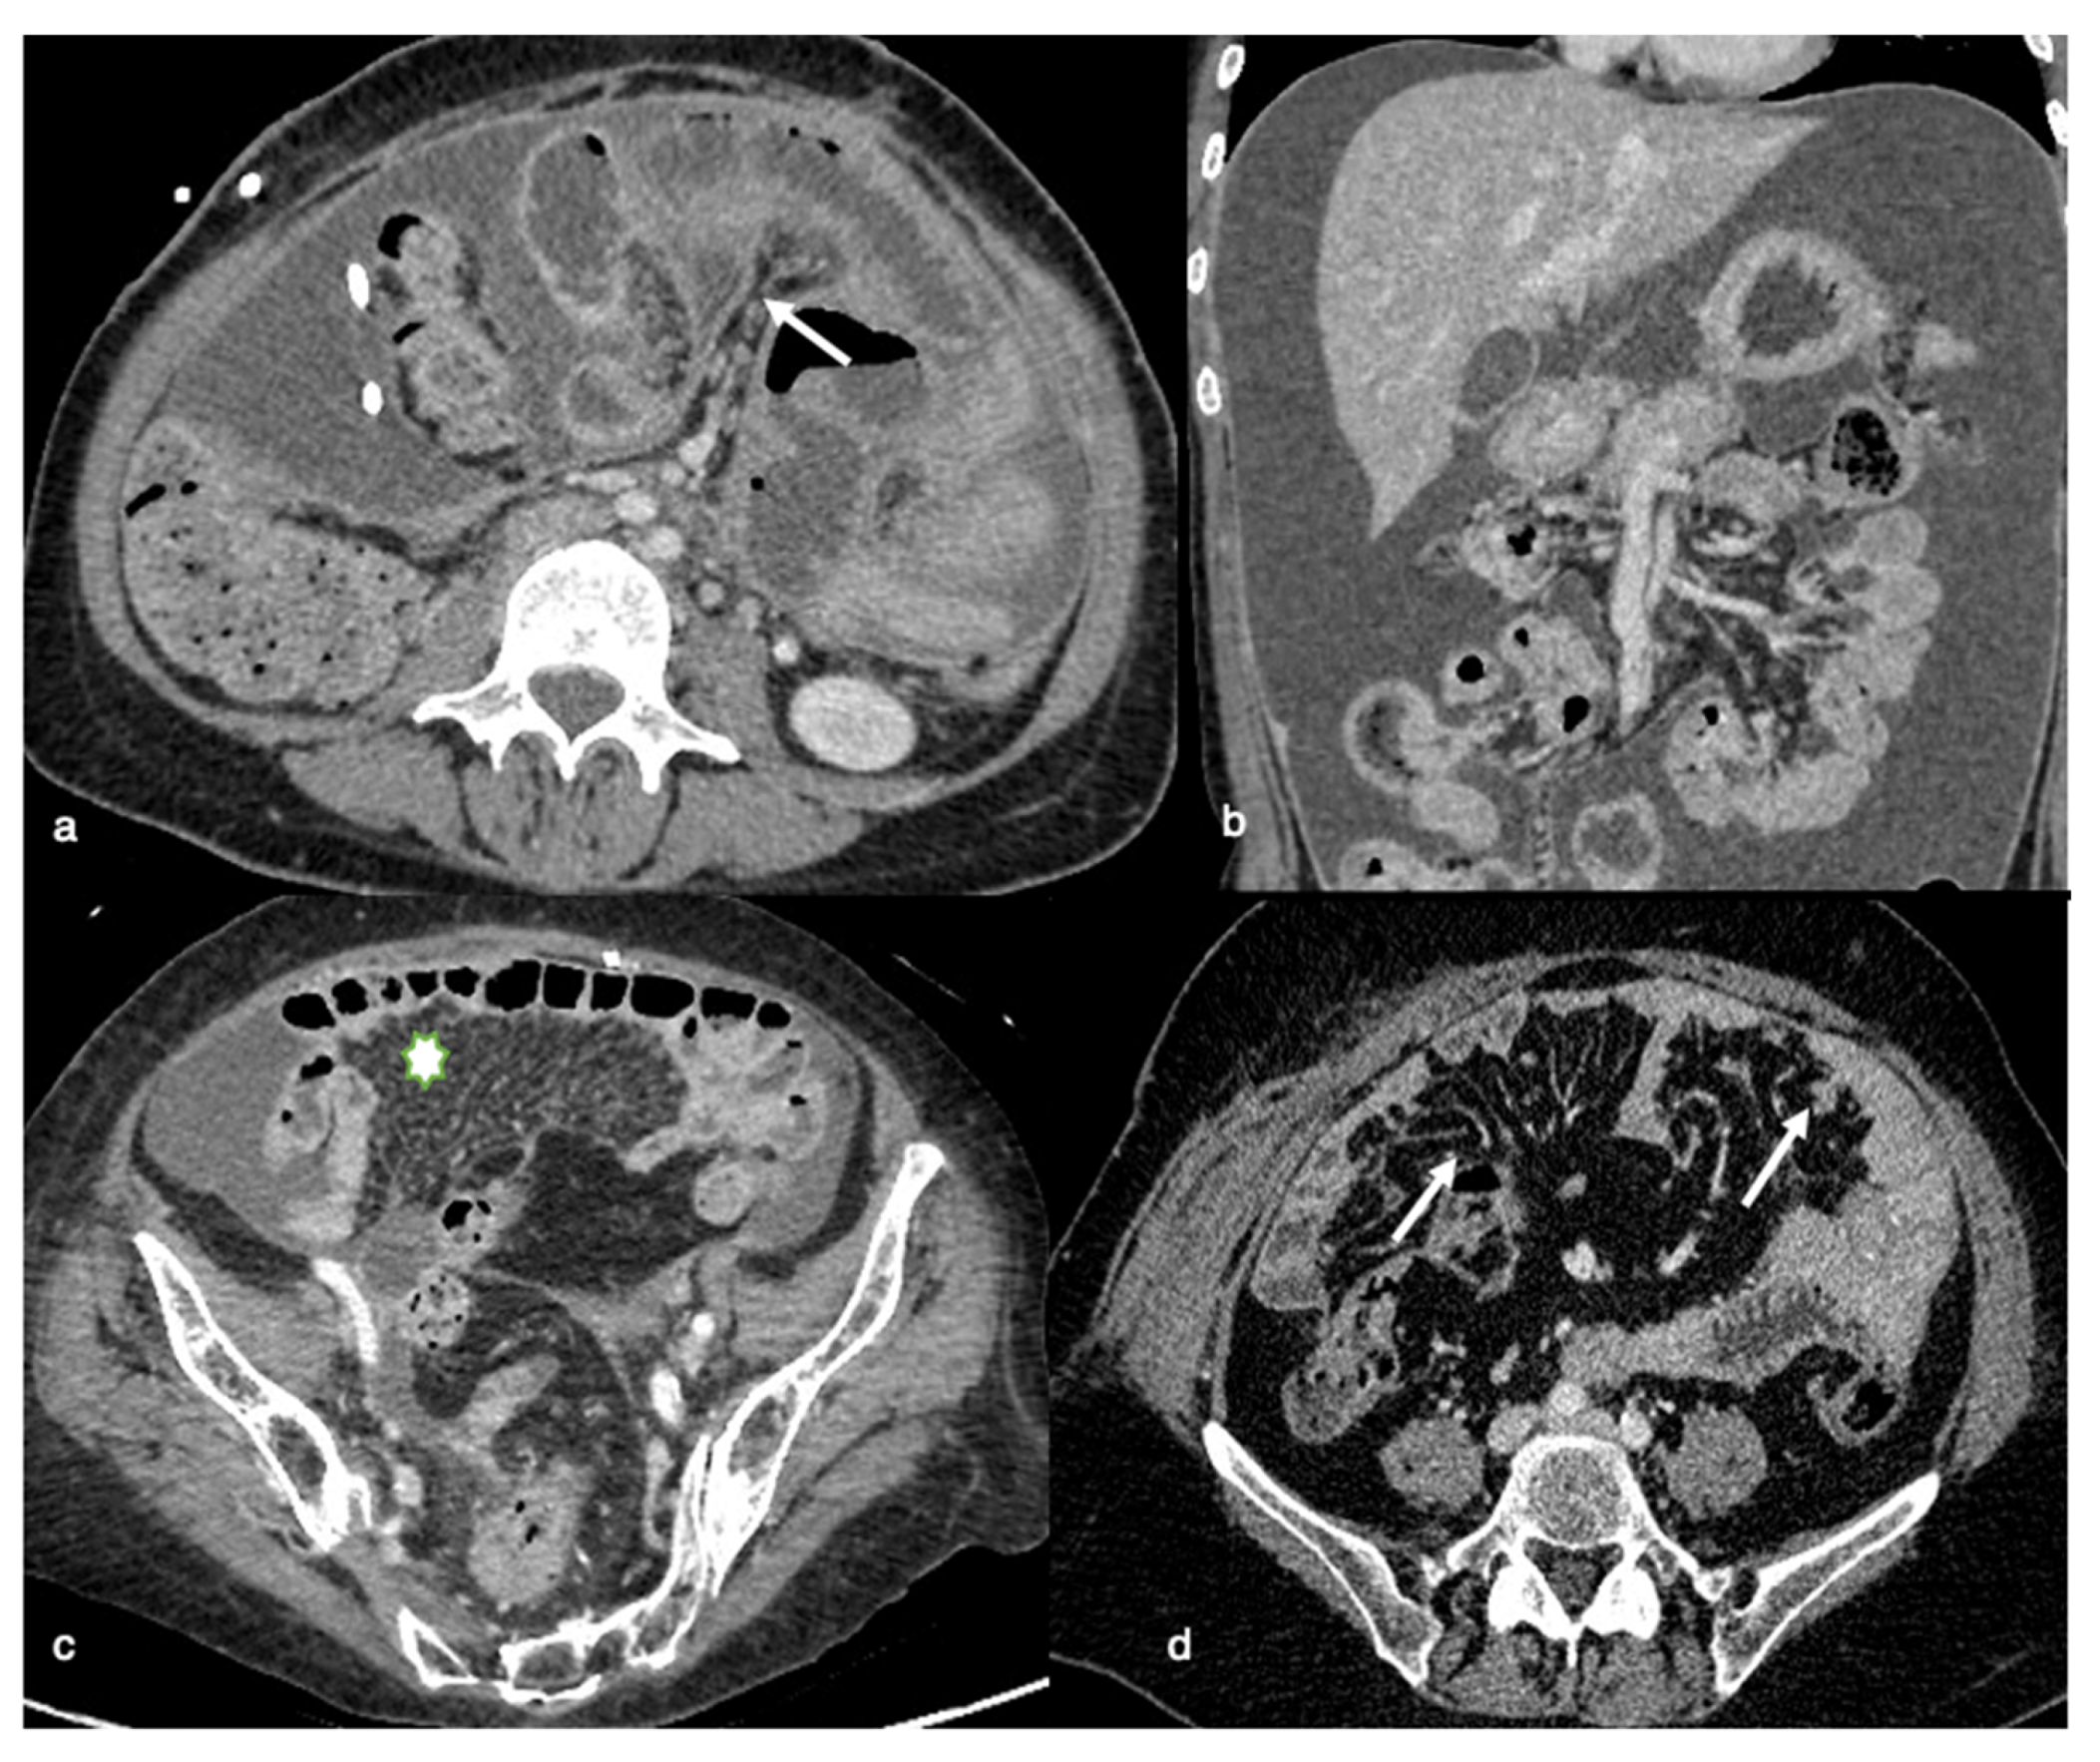

Imaging results in patients with anterior entero-parietal adhesions at the operative site include focal obscuration of pro-peritoneal fat associated with closely adherent omentum and small bowel loops (Figure 6). Indirect symptoms can also be caused by an extrinsic indentation or kink over a bowel loop, which can induce mucosal fold distortion or luminal restriction. Peritoneal adhesion is also assumed as linear or curvilinear soft tissue stands, extending up to another bowel loop or peritoneal surface [18].

Intestinal (sub)occlusion of dilated bowel loops may also be a relative side effect of the laparoscopic approach since it is associated with a greater chance of access injury or iatrogenic bowel lesions (Figure 7). Laparoscopy is challenging in scenarios in which there are diffusely dilated small bowel loops, since the working space available in the pneumoperitoneum is restricted. Furthermore, small bowel manipulation and retraction in this context are associated with an increased risk of serosal tears or enterotomy [19,20].

Chemical peritonitis caused by PIPAC, along with corresponding “burned-like” tissue damage and small bowel edema, can result in a complete loss of small bowel function, even in sub-occlusive disease, and for this reason should be prevented [21].

PIPAC can also be contraindicated in patients with a stiff and coarse abdominal wall as a symptom of broad tumor load of the visceral and parietal peritoneum, with peritoneal space obliteration attributable to omental cake or great nodules (Figure 7). Access to the abdominal cavity is complicated in these cases, and the chance of bleeding complications from these tumor masses is elevated. Large tumors and bulky deposits have a lower response to PIPAC when compared to miliary patterns, likely because of lower drug penetration [22]. In such cases, tumor-associated adhesions are frequently prominent, increasing the likelihood of iatrogenic bowel lesions.

Figure 6. Relative contraindications to PIPAC or laparoscopic approaches. Axial (a) and sagittal MPR (b) contrast-enhanced CT-images show a focal obscuration of pro-peritoneal fat associated with closely adherent omentum and small bowel loops (arrows), indicative of anterior entero-parietal adhesions.

Figure 7. Relative contraindications to PIPAC or laparoscopic approaches. CT axial images can easily detect dilated bowel loops, indicative of intestinal occlusion (a) or diffuse omental thickening (“omental cake”; asterisk) (b). These conditions may represent a relative contraindication to PIPAC, being responsible for complex access to the abdominal cavity with a consequent higher risk for iatrogenic bowel lesions. The presence of omental masses can also potentially reduce treatment efficacy due to difficulties in drug penetration.